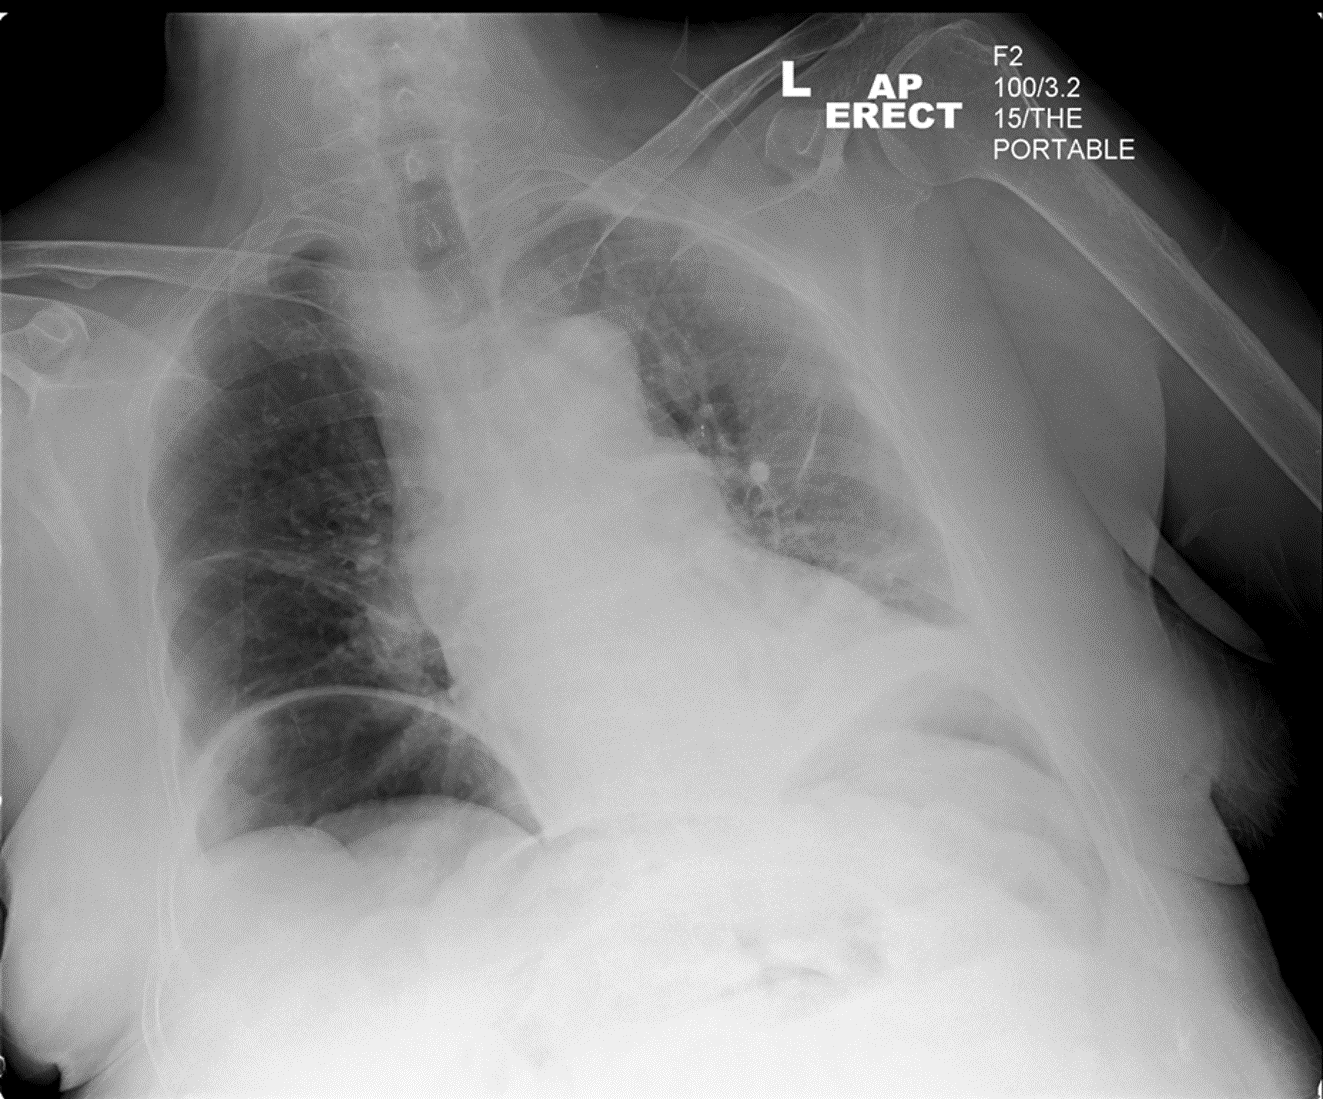

RTC. Passenger. ?pneumothorax

Normal (3)